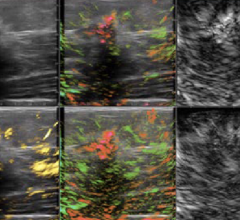

Ultrasound projects developed will focus on engaging with radiology and cardiology departments at Cincinnati Children’s to collaborate on product development and ensure early clinical feedback specific to pediatric use to shape the future of GE HealthCare features and devices, including AI algorithms. GE HealthCare and Cincinnati Children’s will also work together to improve the use of ultrasound to gather measurable data, including development of new technology and clinical evidence for liver imaging techniques.